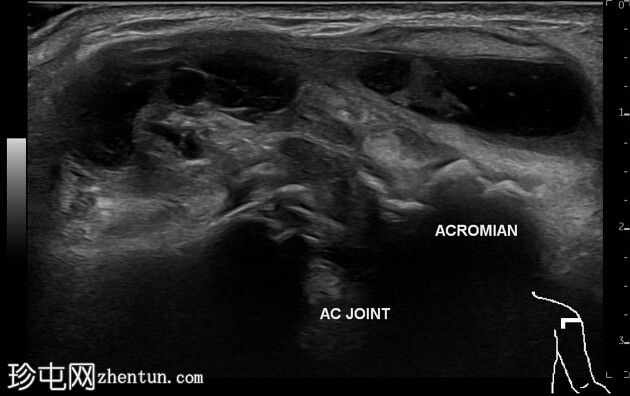

超声

多平面

临床和X线片可见的肿块是一个起源于左侧肩锁关节并位于其上的不规则壁囊肿。囊肿内可见数个等回声至低回声区域,并伴有微小的强回声灶。囊肿周围及间隔可见血流信号。下方的肩锁关节可见关节囊增厚和骨质不规则。

超声显示肩峰肱骨间距缩小,肱二头肌长头在肱二头肌沟内消失,肱二头肌长头肌腱交界处下垂并伴有脂肪浸润,肩胛下肌颅侧纤维全层撕裂,尾侧纤维完整,冈上肌腱和冈下肌腱消失,小圆肌腱变薄且呈低回声,肱骨头软骨变薄,冈上肌-冈下肌脂肪浸润伴体积缩小,小圆肌回声正常但体积增大。